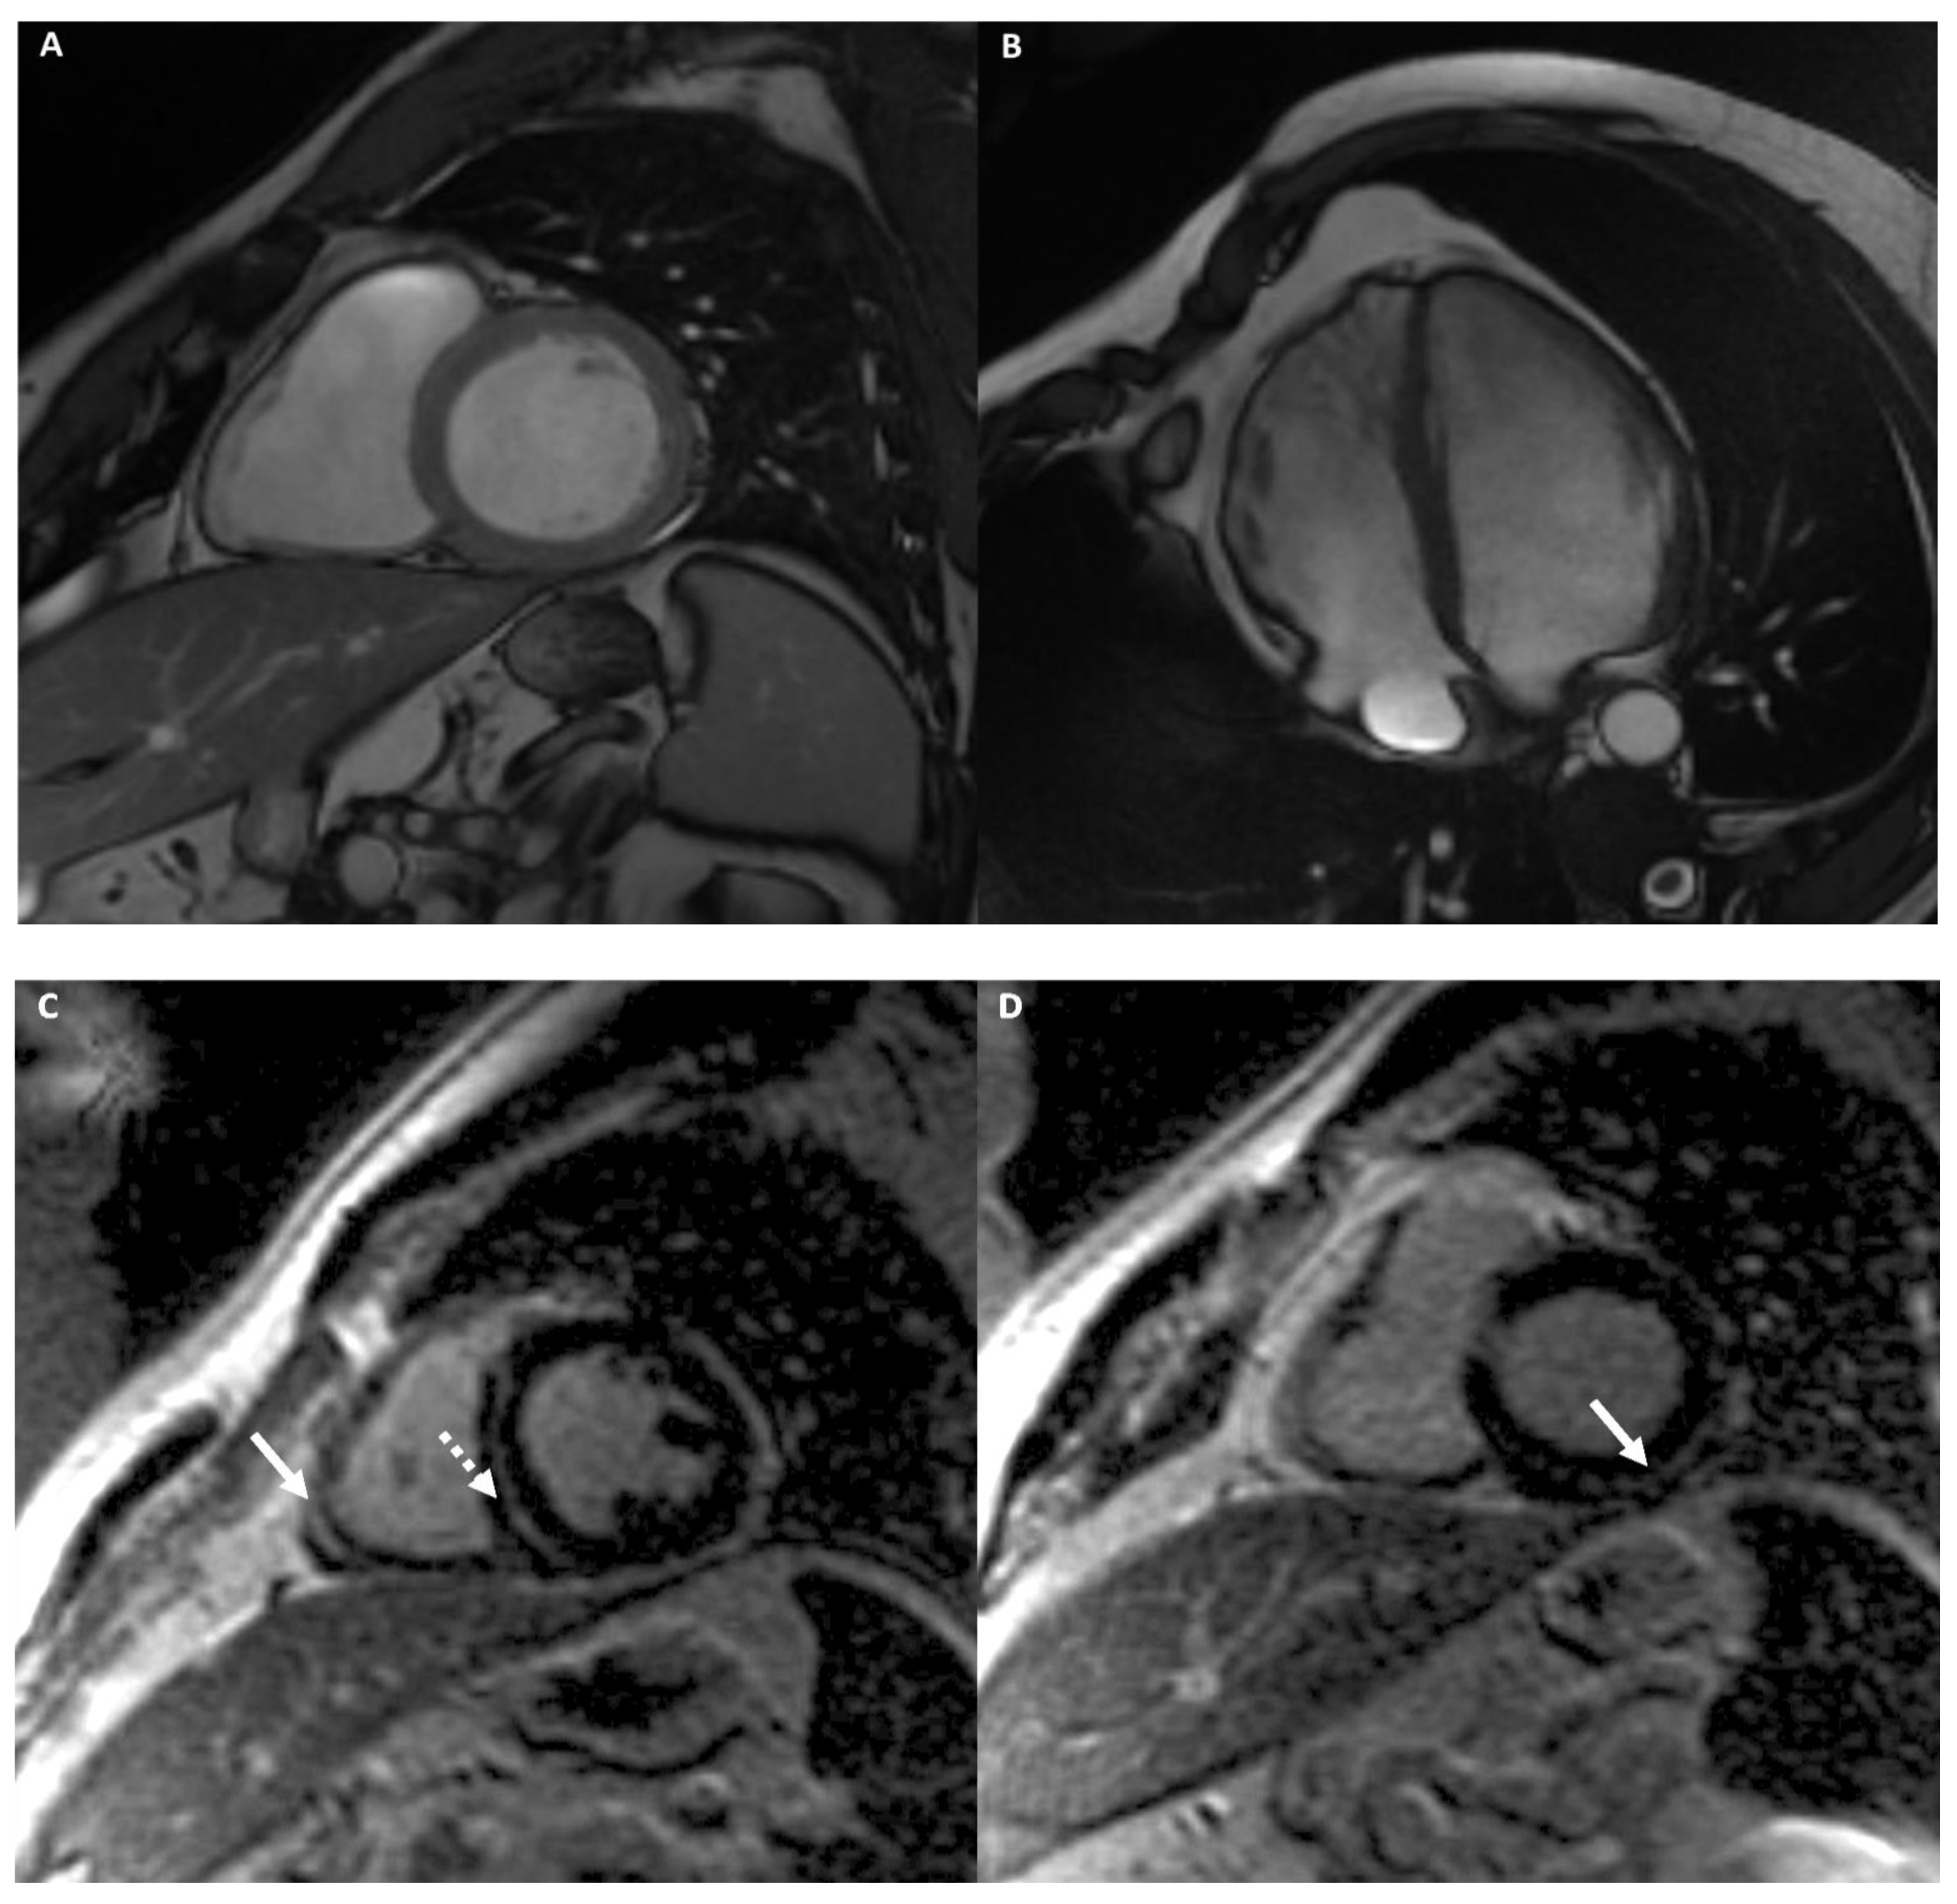

Arrhythmogenic Right Ventricular Cardiomyopathy

- Palumbo, P.; Cannizzaro, E.; Di Cesare, A.; Bruno, F.; Schicchi, N.; Giovagnoni, A.; Splendiani, A.; Barile, A.; Masciocchi, C.; Di Cesare, E. Cardiac magnetic resonance in arrhythmogenic cardiomyopathies. Radiol. Med. 2020, 125, 1087–1101. [Google Scholar] [CrossRef]

- Prior, D. Differentiating Athlete’s Heart from Cardiomyopathies—The Right Side. Heart Lung Circ. 2018, 27, 1063–1071. [Google Scholar] [CrossRef]